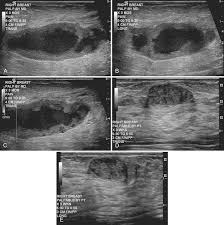

They can also occur in postmenopausal women taking hormone therapy. If the cyst comes back it may be evaluated again with mammogram and ultrasound and it can be drained again. On ultrasound a complex breast cyst will basically be treated in terms of internal echoes presence or absence of posterior enhancement thin septations and a thickened or irregular wall.

Breast cysts do not require treatment unless a cyst is large and painful or otherwise uncomfortable. On ultrasound a complex breast cyst will basically be treated in terms of internal echoes presence or absence of posterior enhancement thin septations and a thickened or irregular wall. A systematic review of the literature on sonographically detected complex breast cysts was carried. Management recommendations for complex cysts were 1-year follow-up in 13 patients 6-month follow-up in 148 sonographically guided aspiration in 82 aspiration with possible core biopsy in 62 and excisional biopsy in three. Your healthcare provider may want to perform a breast cyst aspiration or needle biopsy withdrawing fluid with a needle for analysis. Breast cysts dont require treatment unless a cyst is large and painful or uncomfortable. Not everyone is diagnosed with breast cysts and has treatment before pregnancy or childbirth. Complex breast cysts were estimated to be reported in approximately 5 of breast ultrasound examinations. Breast cysts can also be found in men although this is very rare.